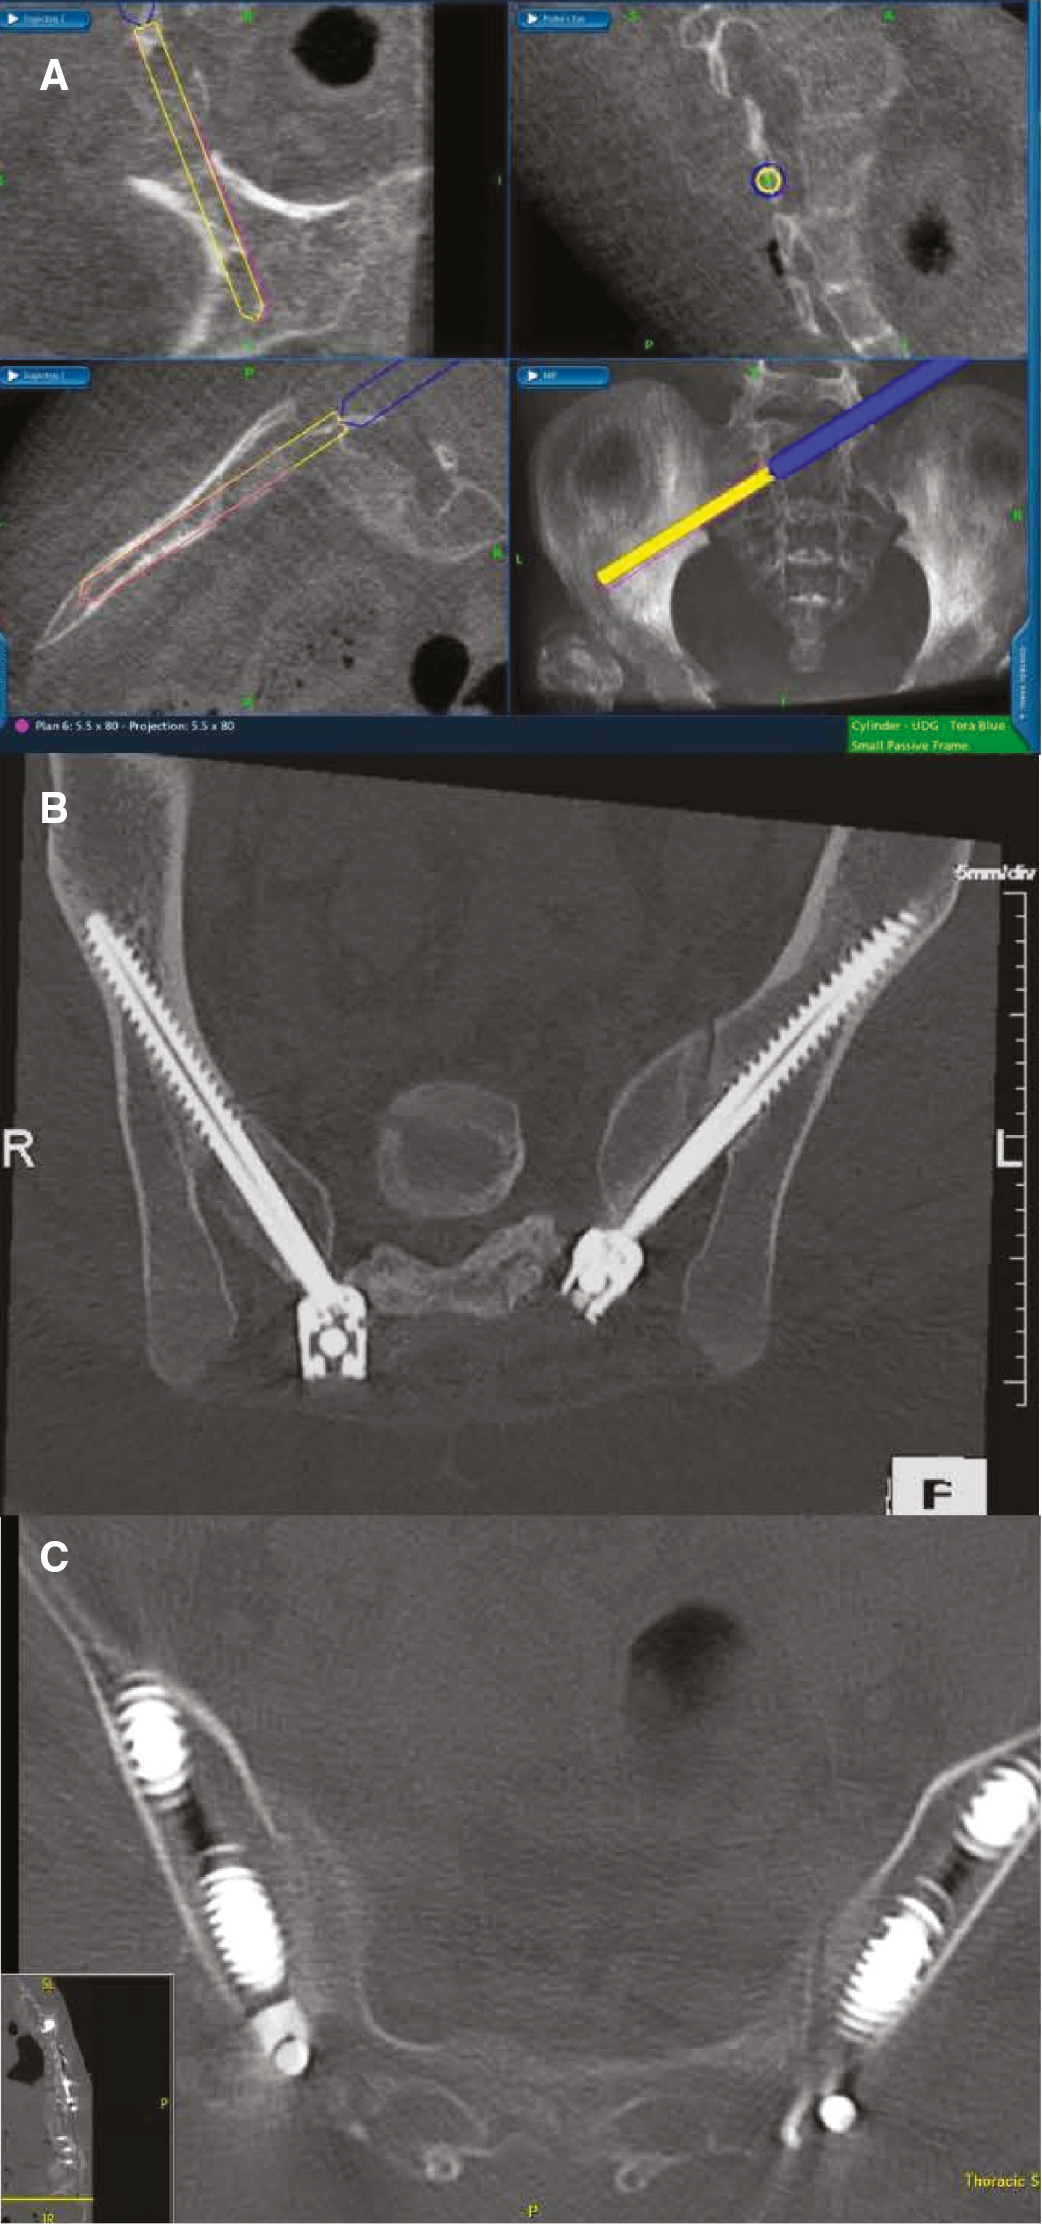

Using the data from the intraoperative or preoperative CT scan, a computerized navigation system is used for screw placement (Stealth, Medtronic, Inc, Louisville, CO; include 7D as well by SeaSpine). Referenced to the intraoperative CT data, the navigation system then generates real-time axial, coronal, and sagittal images depicting the position of the instrument or implant (Figure 2).

Figure 2. CT-guided technique for placement of S2AI screws. A) Computerized navigation system assists in screw placement, generating real-time coronal, axial, and sagittal images depicting the position of the instrument. B) & C) Postoperative axial CT images show optimal screw positioning.